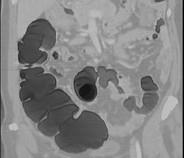

问题 女,56岁,腹胀、腹痛、左下腹包块三月余,无肛门排气,影像检查如图,最可能的诊断是 ( )

选项 A.乙状结肠Crohn病 B.乙状结肠结核 C.乙状结肠腺癌 D.乙状结肠淋巴瘤 E.乙状结肠息肉

答案 C